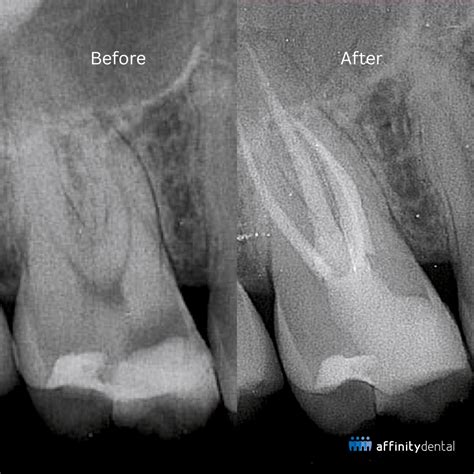

Root Canal Before And After

Comparing the Condition Before and After Treatment

Visualizing the root canal before and after transformation helps patients understand why this procedure is so beneficial. Before the procedure, the tooth is often compromised, sensitive, and actively fighting an infection. After the procedure, the tooth is structurally sound, infection-free, and aesthetically restored.